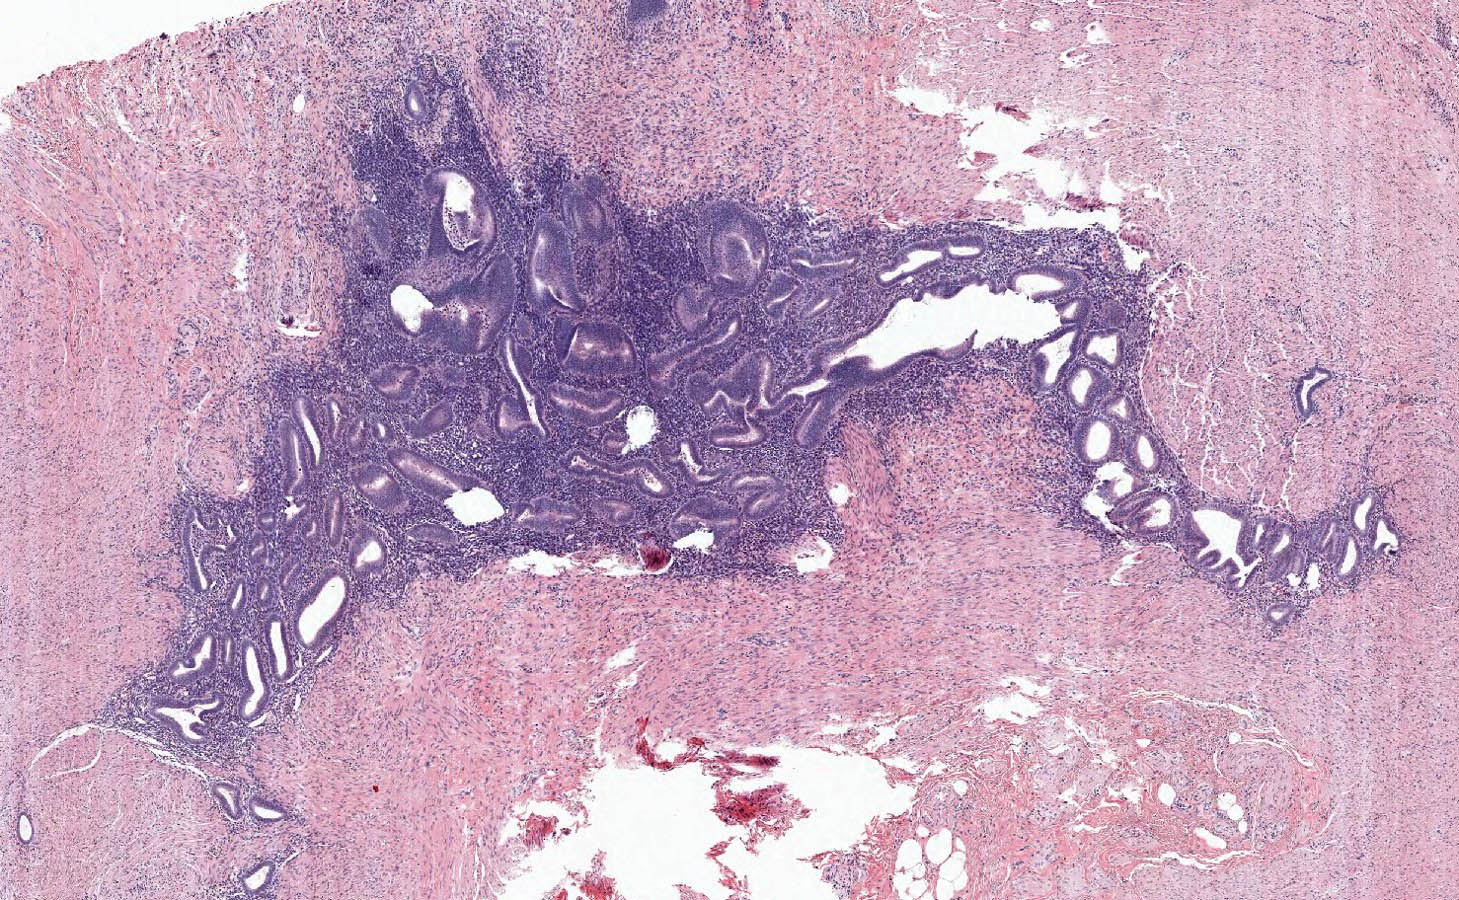

Microscopic (histologic) description

- Variable acute inflammation with predominance of neutrophils; involves some or all layers of the appendiceal wall

- Process may be divided into acute focal, acute suppurative, gangrenous and perforative

- Early lesions display mucosal erosions and scattered crypt abscesses

- Later, the inflammation extends into the lamina propria and collections of neutrophils are also seen in the lumen

- Mural necrosis in gangrenous appendicitis

- Process may be divided into acute focal, acute suppurative, gangrenous and perforative

Microscopic (histologic) images

- Appendiceal endometriosis:

- Typically has a nonspecific presentation; pain may wax and wane with the menstrual cycle

- Most often affects the serosa or muscularis propria and is accompanied by abundant fibrosis and adhesions

- Microscopically, consists of endometrial type glands and stroma associated hemosiderin deposition and a fibroblastic response (Afr Health Sci 2008;8:196)

Practice question #2

A 35 year old woman presented with localized right lower quadrant abdominal pain for 1 day. She also presented with nausea, vomiting, menorrhagia and dizziness. She reported that she was actively menstruating and that these symptoms typically occurred monthly with menstruation but had been particularly severe in that month. CT scan showed thick walled appendix consistent with acute appendicitis. She underwent an appendectomy. The H&E images are shown above. Which of the following is the most likely diagnosis?

- Acute appendicitis

- Appendiceal diverticulitis

- Appendiceal endometriosis

- Interval appendicitis